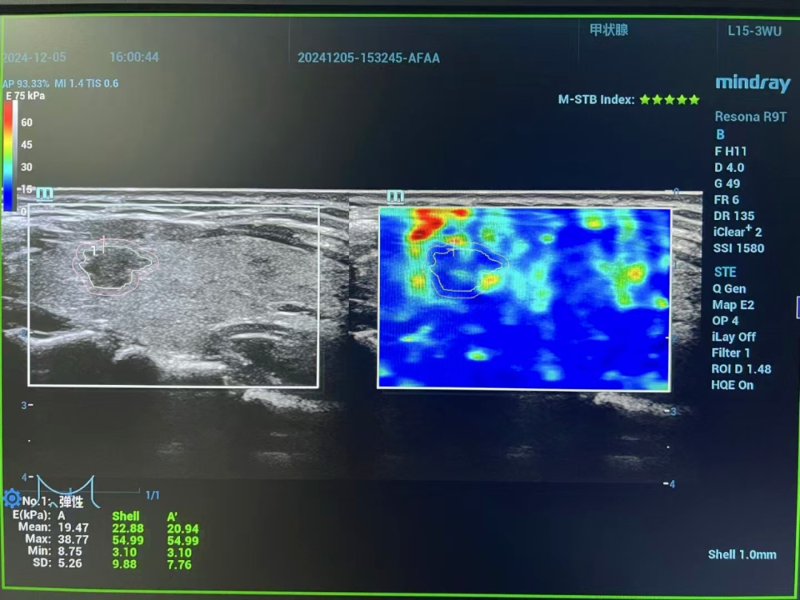

△術前評估

術前評估階段,專家團隊啟用高分辨率頸部超聲與先進磁共振成像技術,全方位、多維度掃描剖析。影像數據精準揭示:李女士左側甲狀腺結節小于1厘米,其包膜間距超2毫米,周邊組織未現侵襲跡象,淋巴結轉移亦無跡可尋。經嚴格篩選,甲狀腺微小乳頭狀癌微波消融手術指征確鑿無疑,為后續精準施治筑牢根基。